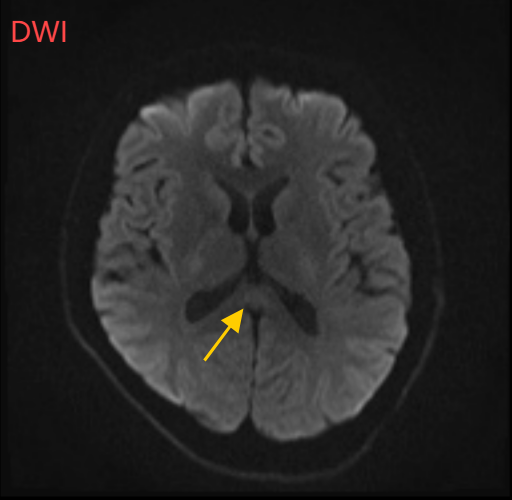

医生摇摇头,经过头部磁共振平扫、弥散、增强影像等检查,医生诊断,小董是得了一种比较少见的病症:可逆性胼胝体压部综合征。

如果把大脑比作一座城市,胼胝体就是连接左右脑的“跨海大桥”,而胼胝体压部正是桥上的“核心枢纽”。当它因酒精、熬夜或感染“肿了”,大脑信号就会“堵车”,引发一系列“故障”。

“压部”病变:胼胝体压部是大脑里的“视觉总监”,眼睛所看到的信息传送到大脑后,由它负责反应整合成图像在脑海中呈现。“压部”发生病变后,就像电视机信号接收不良,屏幕出现雪花一样,眼睛视物就会受到影响。

除了“压部”,胼胝体的其他部位也有病变,所以小董才会出现幻听、手抖等症状。